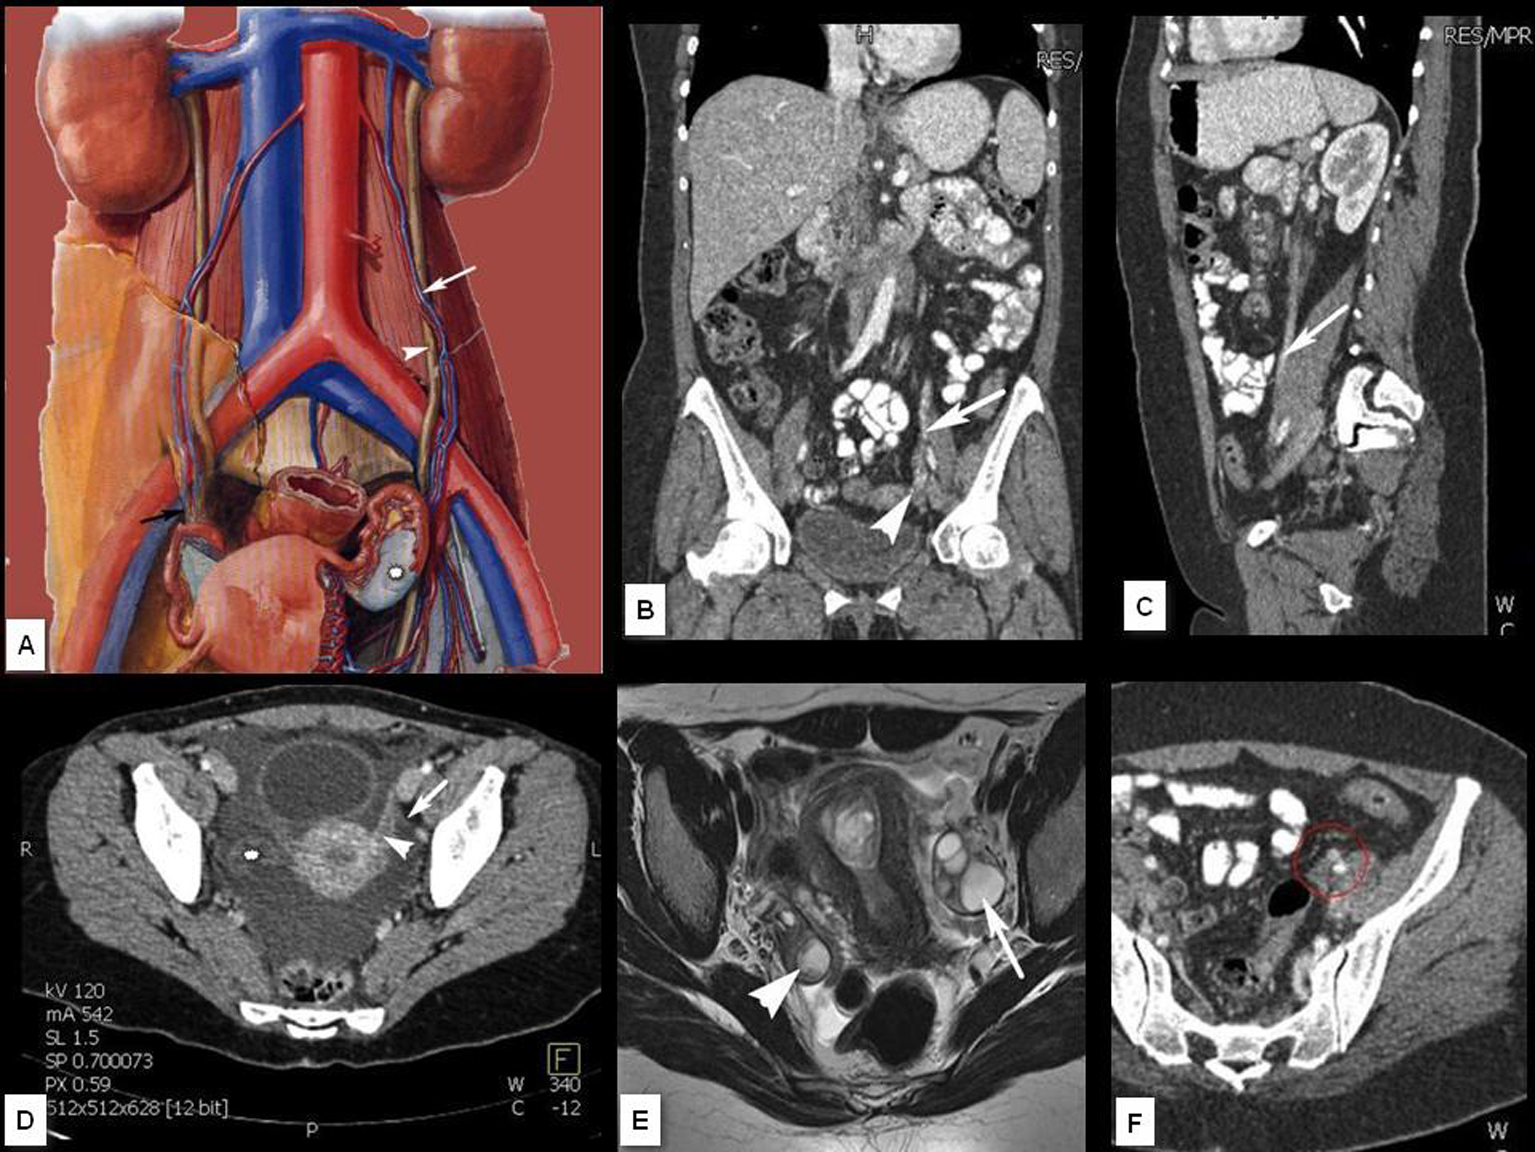

En el contexto del abordaje multidisciplinar para el diagnóstico y tratamiento del cáncer de ovario, la aportación del radiólogo incluye cuatro puntos fundamentales que son: identificación de la lesión, caracterización, estudio de extensión y valoración evolutiva. En el presente trabajo se describen los hallazgos y claves diagnósticas en TCMD (Tomografía Computarizada multidetector) y RM (Resonancia Magnética), la aportación e indicación de otras tecnologías como el PET (Tomografía por Emisión de Positrones) y se esbozan las técnicas emergentes basadas en imagen funcional (estudios dinámicos con contraste en RM y estudios de difusión por RM).Descargas

10. PANNU HK, BRISTOW RE, MONTZ FJ, FISHMAN EK. Multidetector CT of peritoneal carcinomatosis from ovarian cancer. Radiographics 2003; 23: 687-701.

12. WOODWARD PJ, HOSSEINZADEH K, SAENGER JS. From the archives of the AFIP. Radiologic staging of ovarian carcinoma with patologic correlation. Radiographics 2004; 24: 225-246.